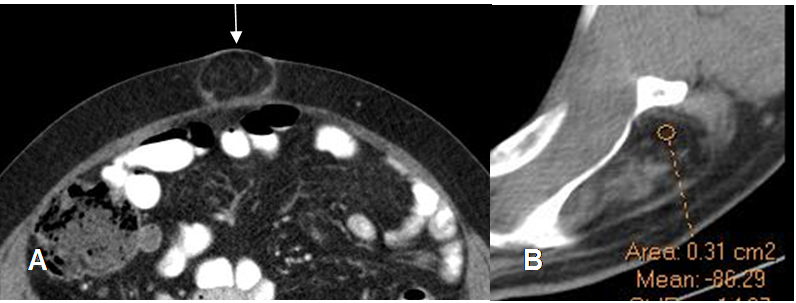

Fig 160. Lipoma.

A: TAC axial. Imagen redondeada e hipodensa en la pared abdominal, con densidad similar a la grasa, por lipoma.

B: TAC axial. Lipoma en el músculo infraespinoso, con densidad negativa. (-80 UH).